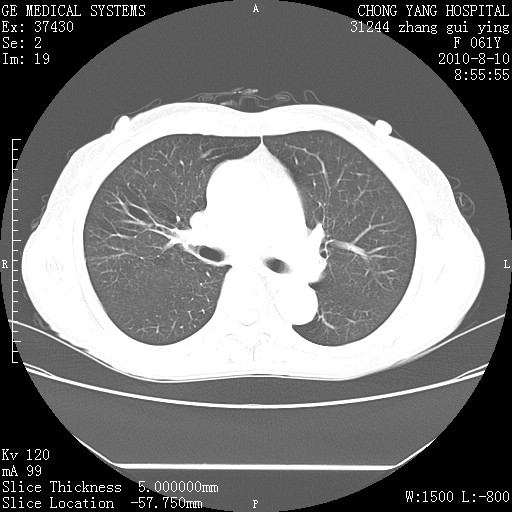

标题: CT28314:F61Y胸部增强,发热咳嗽一周入院,后面的为一周前平 [打印本页]

标题: CT28314:F61Y胸部增强,发热咳嗽一周入院,后面的为一周前平

1、支持考虑右侧中央型肺癌伴右肺中叶节段性不张及下叶支气管黏液痰栓    2、左肺上叶舌段感染。

支持右下肺中央型肺癌并左上肺感染.

确切的说:1:右肺下叶中心型肺癌侵及中叶支气管并中叶不张,纵膈淋巴结转移。2:左肺舌叶炎症。3:右侧胸腔少量积液

1:右肺下叶中心型肺癌侵及中叶支气管并中叶不张,纵膈淋巴结转移。2:左肺舌叶炎症。3:右侧胸腔少量积液。支持!

右肺下叶中心型肺癌侵及中叶支气管并中叶不张,纵膈淋巴结转移。2:左肺舌叶炎症。3:右侧胸腔少量积液